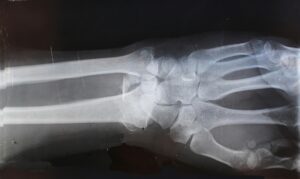

Medical scans are excellent at detecting:

• Fractures

• Tears

• Major structural changes

But they don’t show everything.

Scans don’t measure:

• How well your joints are moving

• Muscle tension patterns

• Subtle compensations in your posture or movement

• How your nervous system is handling stress

Old injuries may reduce movement in one area of the spine. The body adapts by asking other areas to move more. Over time, this creates imbalance.

And imbalance doesn’t always show up on imaging but you can definitely feel it.